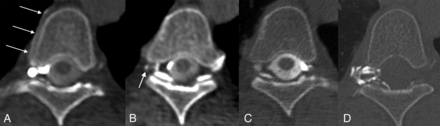

Right T5 CVF and subsequent treatment. A, Axial right lateral decubitus CTM image shows a right foraminal meningeal diverticulum and a hyperdense right paraspinal vein (arrows). B, Axial right lateral decubitus CTM image obtained immediately caudal to (A) shows opacification of a small radicular vein (arrow). C, Axial left lateral decubitus CTM image shows no abnormality. D, Axial posttreatment CT shows contrast-opacified fibrin sealant filling the foramen and extending into the epidural space of vertebral canal.